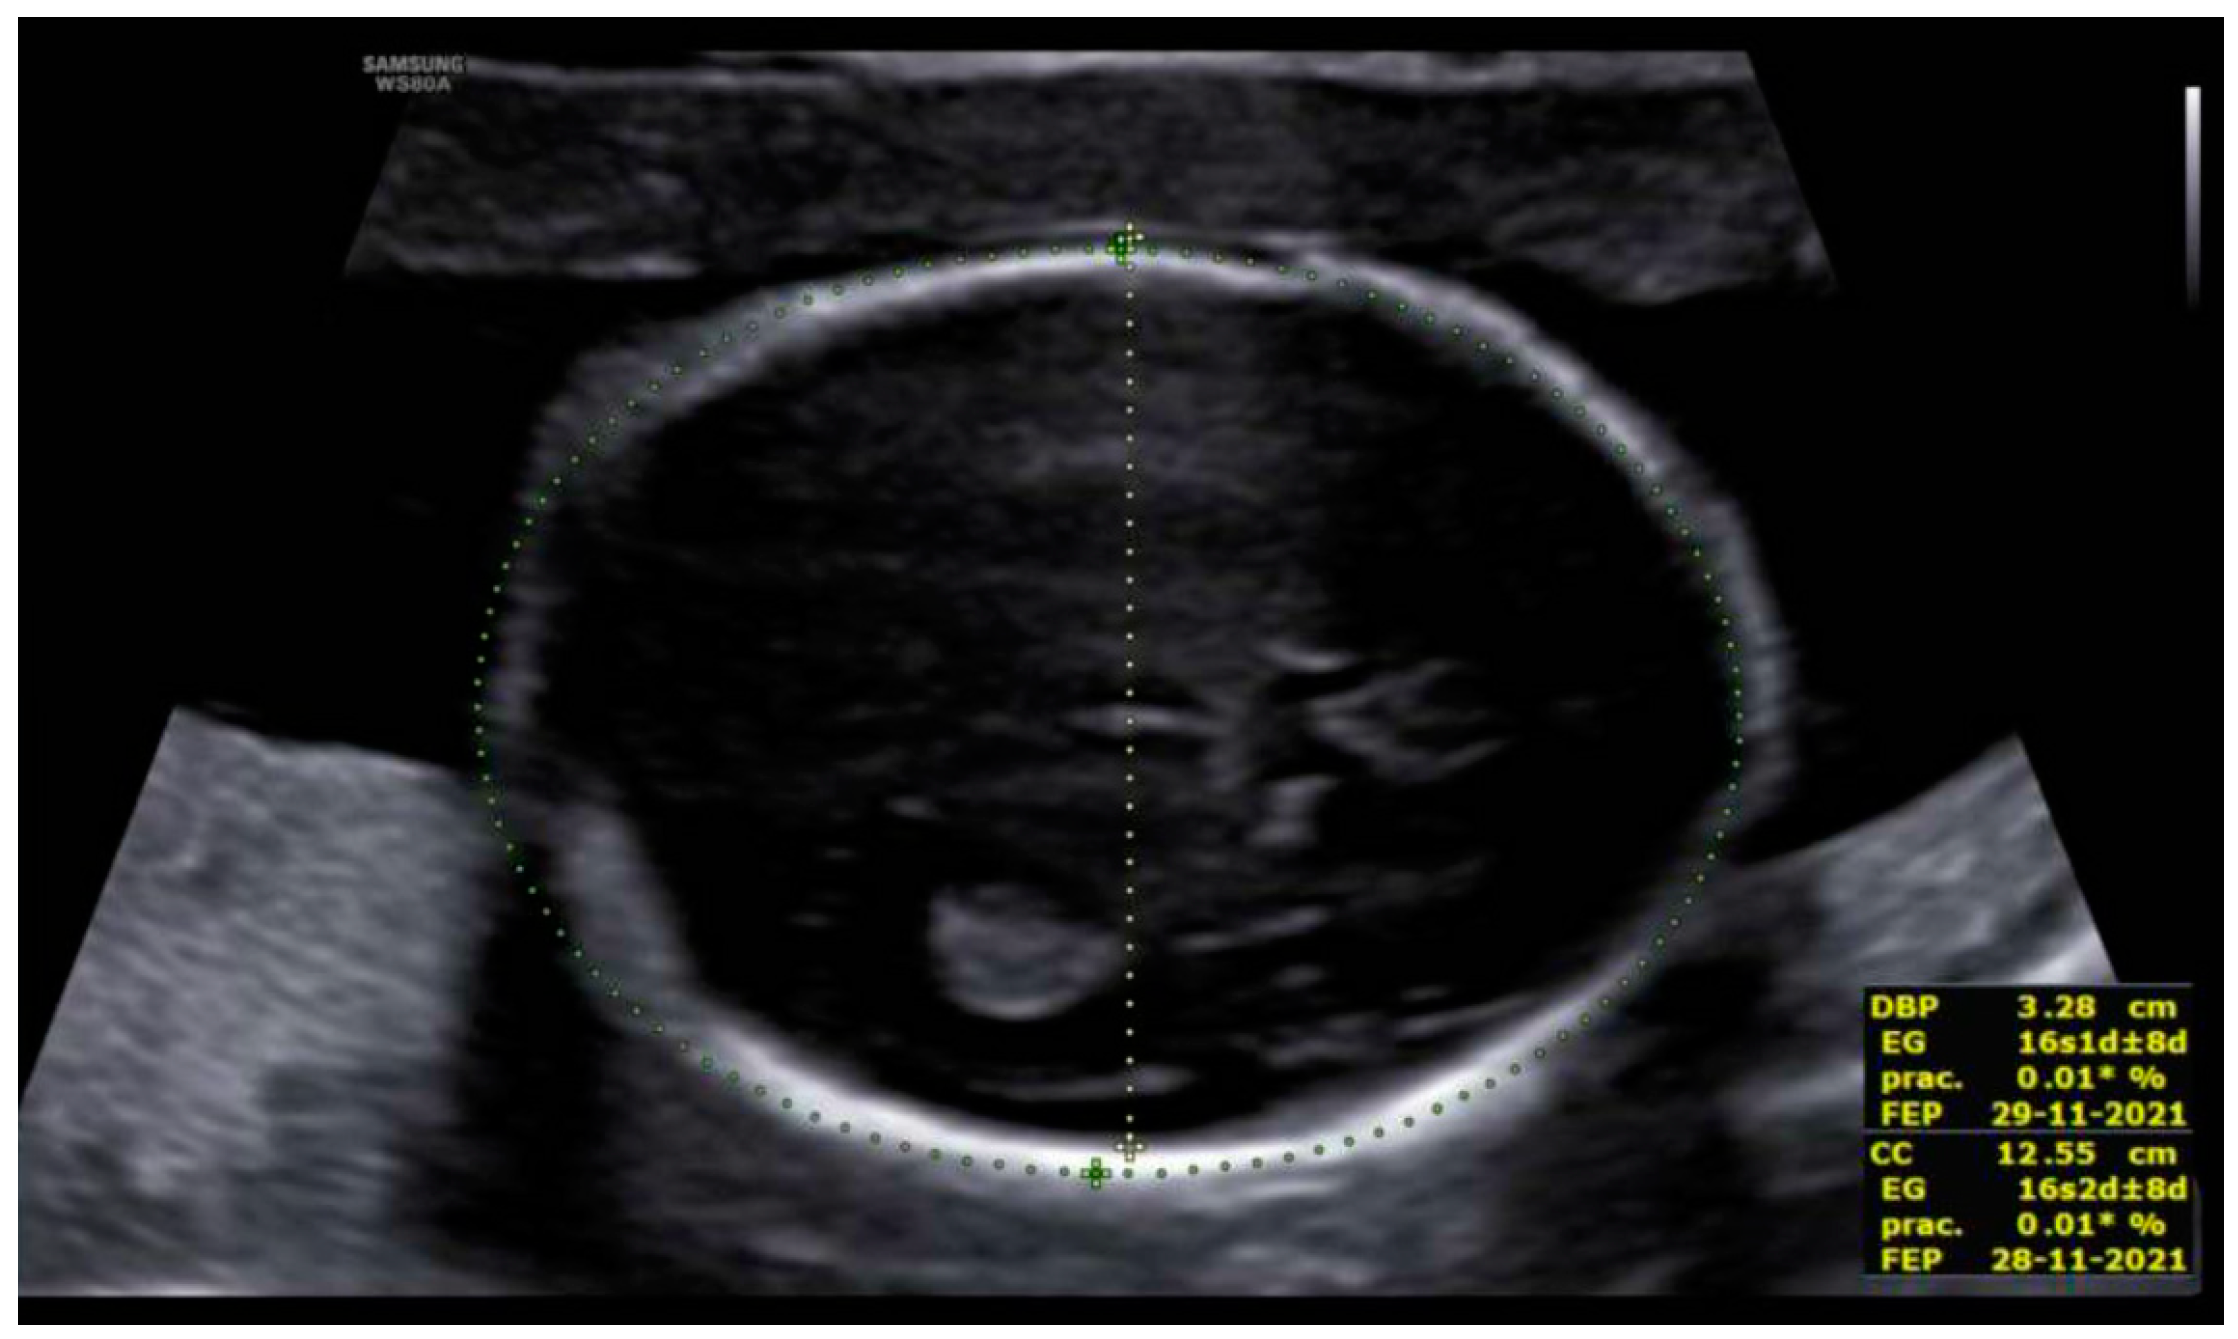

3. Results: Case Presentation